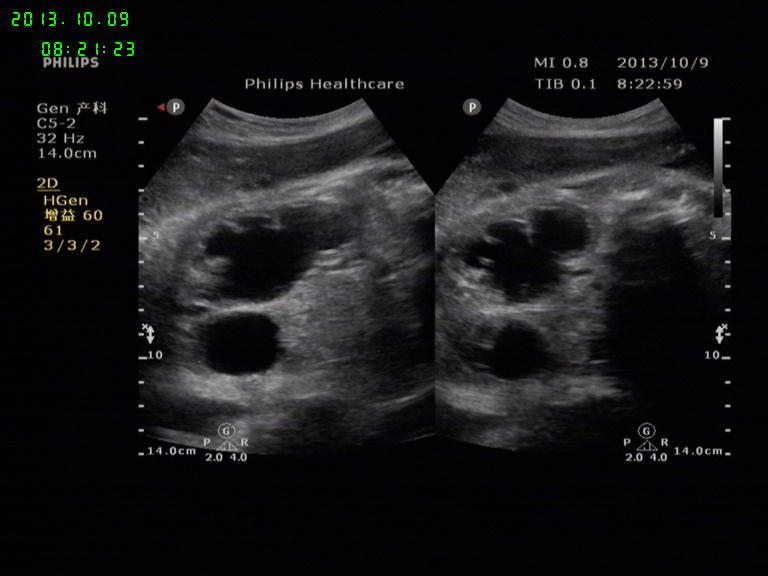

胎儿左肾积水

孕38周胎儿,左肾积水,右肾大小形态正常,羊水量AFI:20.5cm

右肾积水好多,曾经见过一例,产后1周做尿路造影考虑是重复肾

不好意思,第二张标记错了。